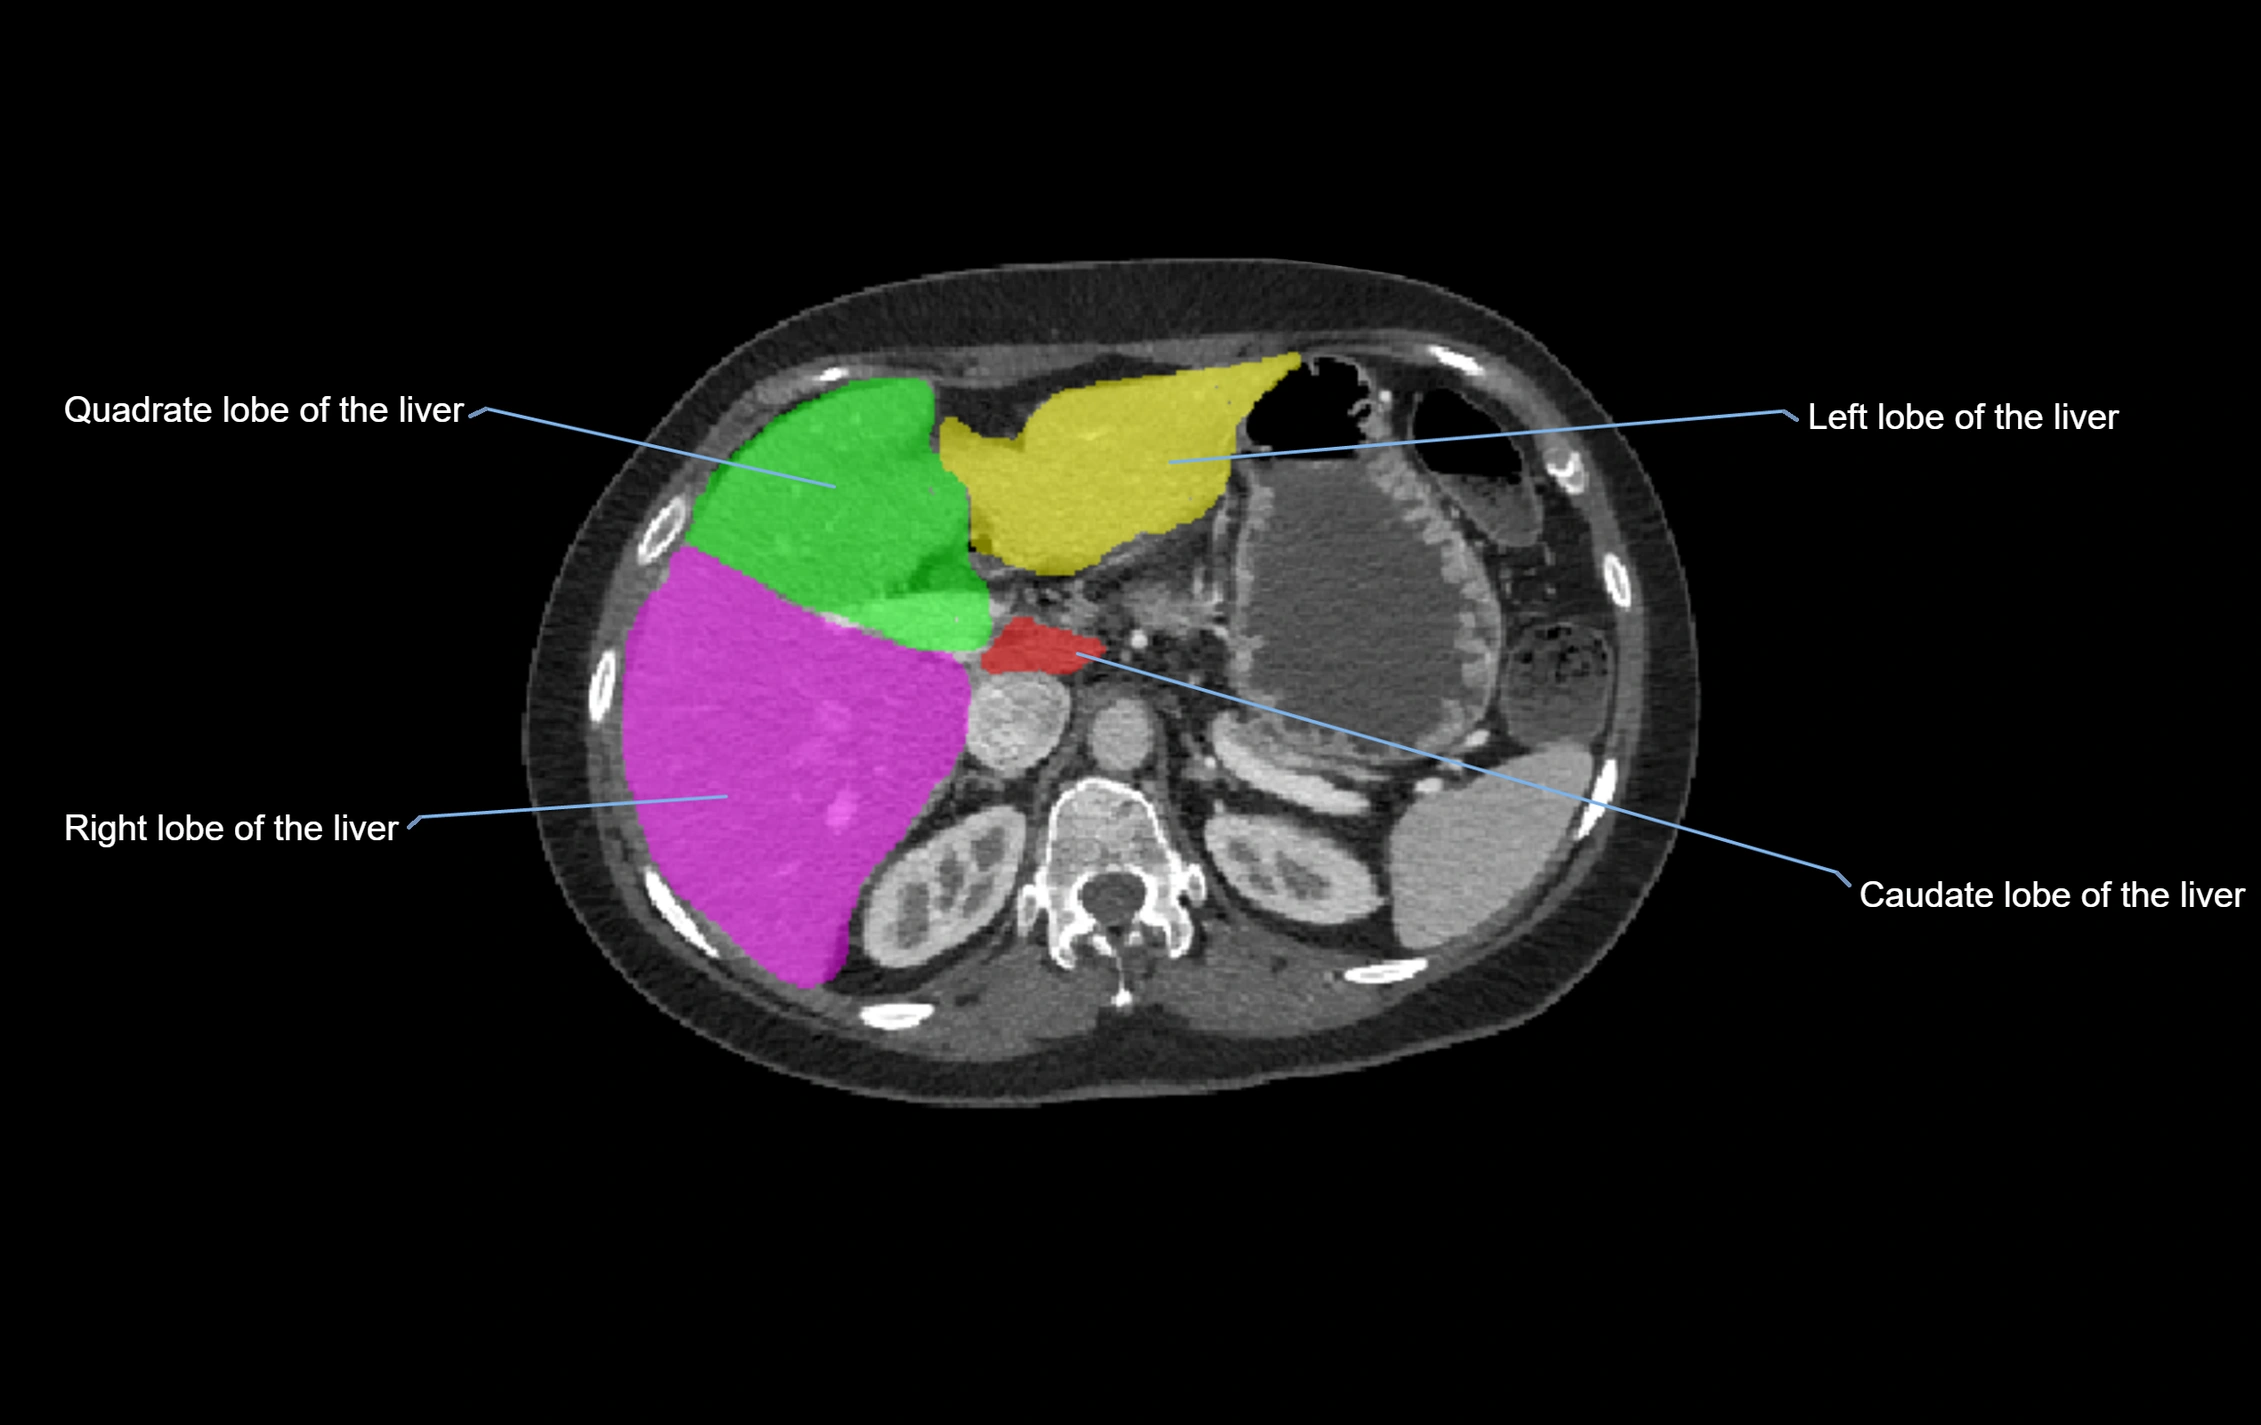

The caudate lobe of the liver is a distinct anatomical subdivision of the liver, designated as segment I in Couinaud’s classification. It lies on the posterior surface of the liver, between the fissure for the ligamentum venosum (left boundary) and the groove for the inferior vena cava (IVC) (right boundary). Superiorly, it is related to the posterior liver surface, and inferiorly it is separated from the left lobe by the porta hepatis.

The caudate lobe is unique because it receives dual portal venous and arterial inflow from both the right and left portal veins and hepatic arteries. It also has independent venous drainage directly into the IVC via multiple small hepatic veins, unlike other lobes that drain through the three main hepatic veins.

CT Image

image